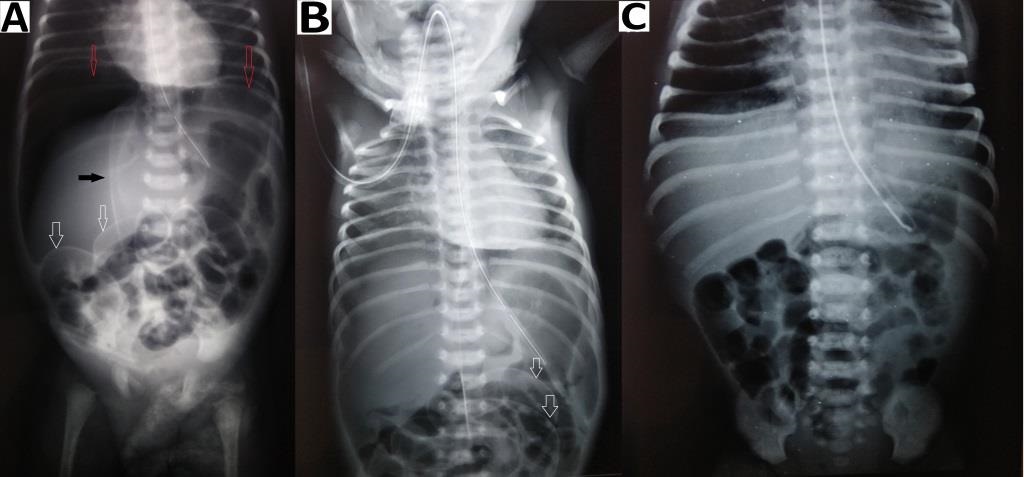

Figure 4

Abdominal radiographs (erect) (A) showing gas under the diaphragm, absence of gas-filled bowel loops, endotracheal tube in-situ, and features of pneumonitis; supine image (B) also showing pneumothorax (red arrow). Pneumoscrotum (yellow arrow) is appreciable in both images (A and B).

Pneumoperitoneum with air under both the domes of the diaphragm was seen in all 4 patients on erect abdominal radiographs (Fig. 1)(Fig. 2)(Fig. 3)(Fig. 4). There was an absence of free fluid in the peritoneal cavity evident by the absence of air-fluid level in the peritoneal (abdominal) cavity i.e. outside bowel loops in all the patients. Dilated small bowel loops were seen in 3 out of 4 patients. Rigler sign or double-wall sign was present in 3 patients. Radiographic evidence of pneumothorax (simultaneously present with pneumoperitoneum) was seen in 1 patient (Fig. 4). Pneumoscrotum was appreciated in 2 patients (Fig. 3)(Fig. 4).

Pneumoperitoneum in a neonate is classically due to GI perforation and necrotizing enterocolitis (NEC).[3], [4] Pneumoperitoneum is usually diagnosed by an erect abdominal radiograph showing free air under the domes of the diaphragm. In the neonates the other radiographic signs include, (a) rounded or oval lucency over the upper abdomen in the supine position, (b) increased lucency i.e. triangular or a semilunar collection of air anterior to the abdominal viscera or above the liver in lateral decubitus position, (c) large volume of free air may give rise to the football sign, where the air outlines the whole of the peritoneal cavity and under the surface of the diaphragm, (d) the lacing of the football i.e. outlining of falciparum ligament of the liver against the radiolucency of free abdominal air on supine view [4], [5], [6] (e) Rigler sign or double-wall sign is free gas on both sides of the bowel wall,[4], [5] (f) pneumoscrotum has been explained due to presence of patent processus vaginalis and passage of air from the peritoneal cavity into the scrotum.[3], [5], [6]

In case of spontaneous pneumoperitoneum, the onset is abrupt usually following mechanical ventilation.[1], [2], [3] The pathogenesis of spontaneous pneumoperitoneum is an air-leak from the lungs as shown in the flowchart (Fig. 5). This is more common with high and prolonged airway pressure during mechanical ventilation or CPAP. In our study, the condition was preceded by mechanical ventilation in 75% (3), while it was 55.56% in our previous study.[3] The presence of pneumothorax (as seen in one of our cases) or pneumomediastinum immediately before or simultaneously with pneumoperitoneum is an indicator of spontaneous pneumoperitoneum.[3], [10]